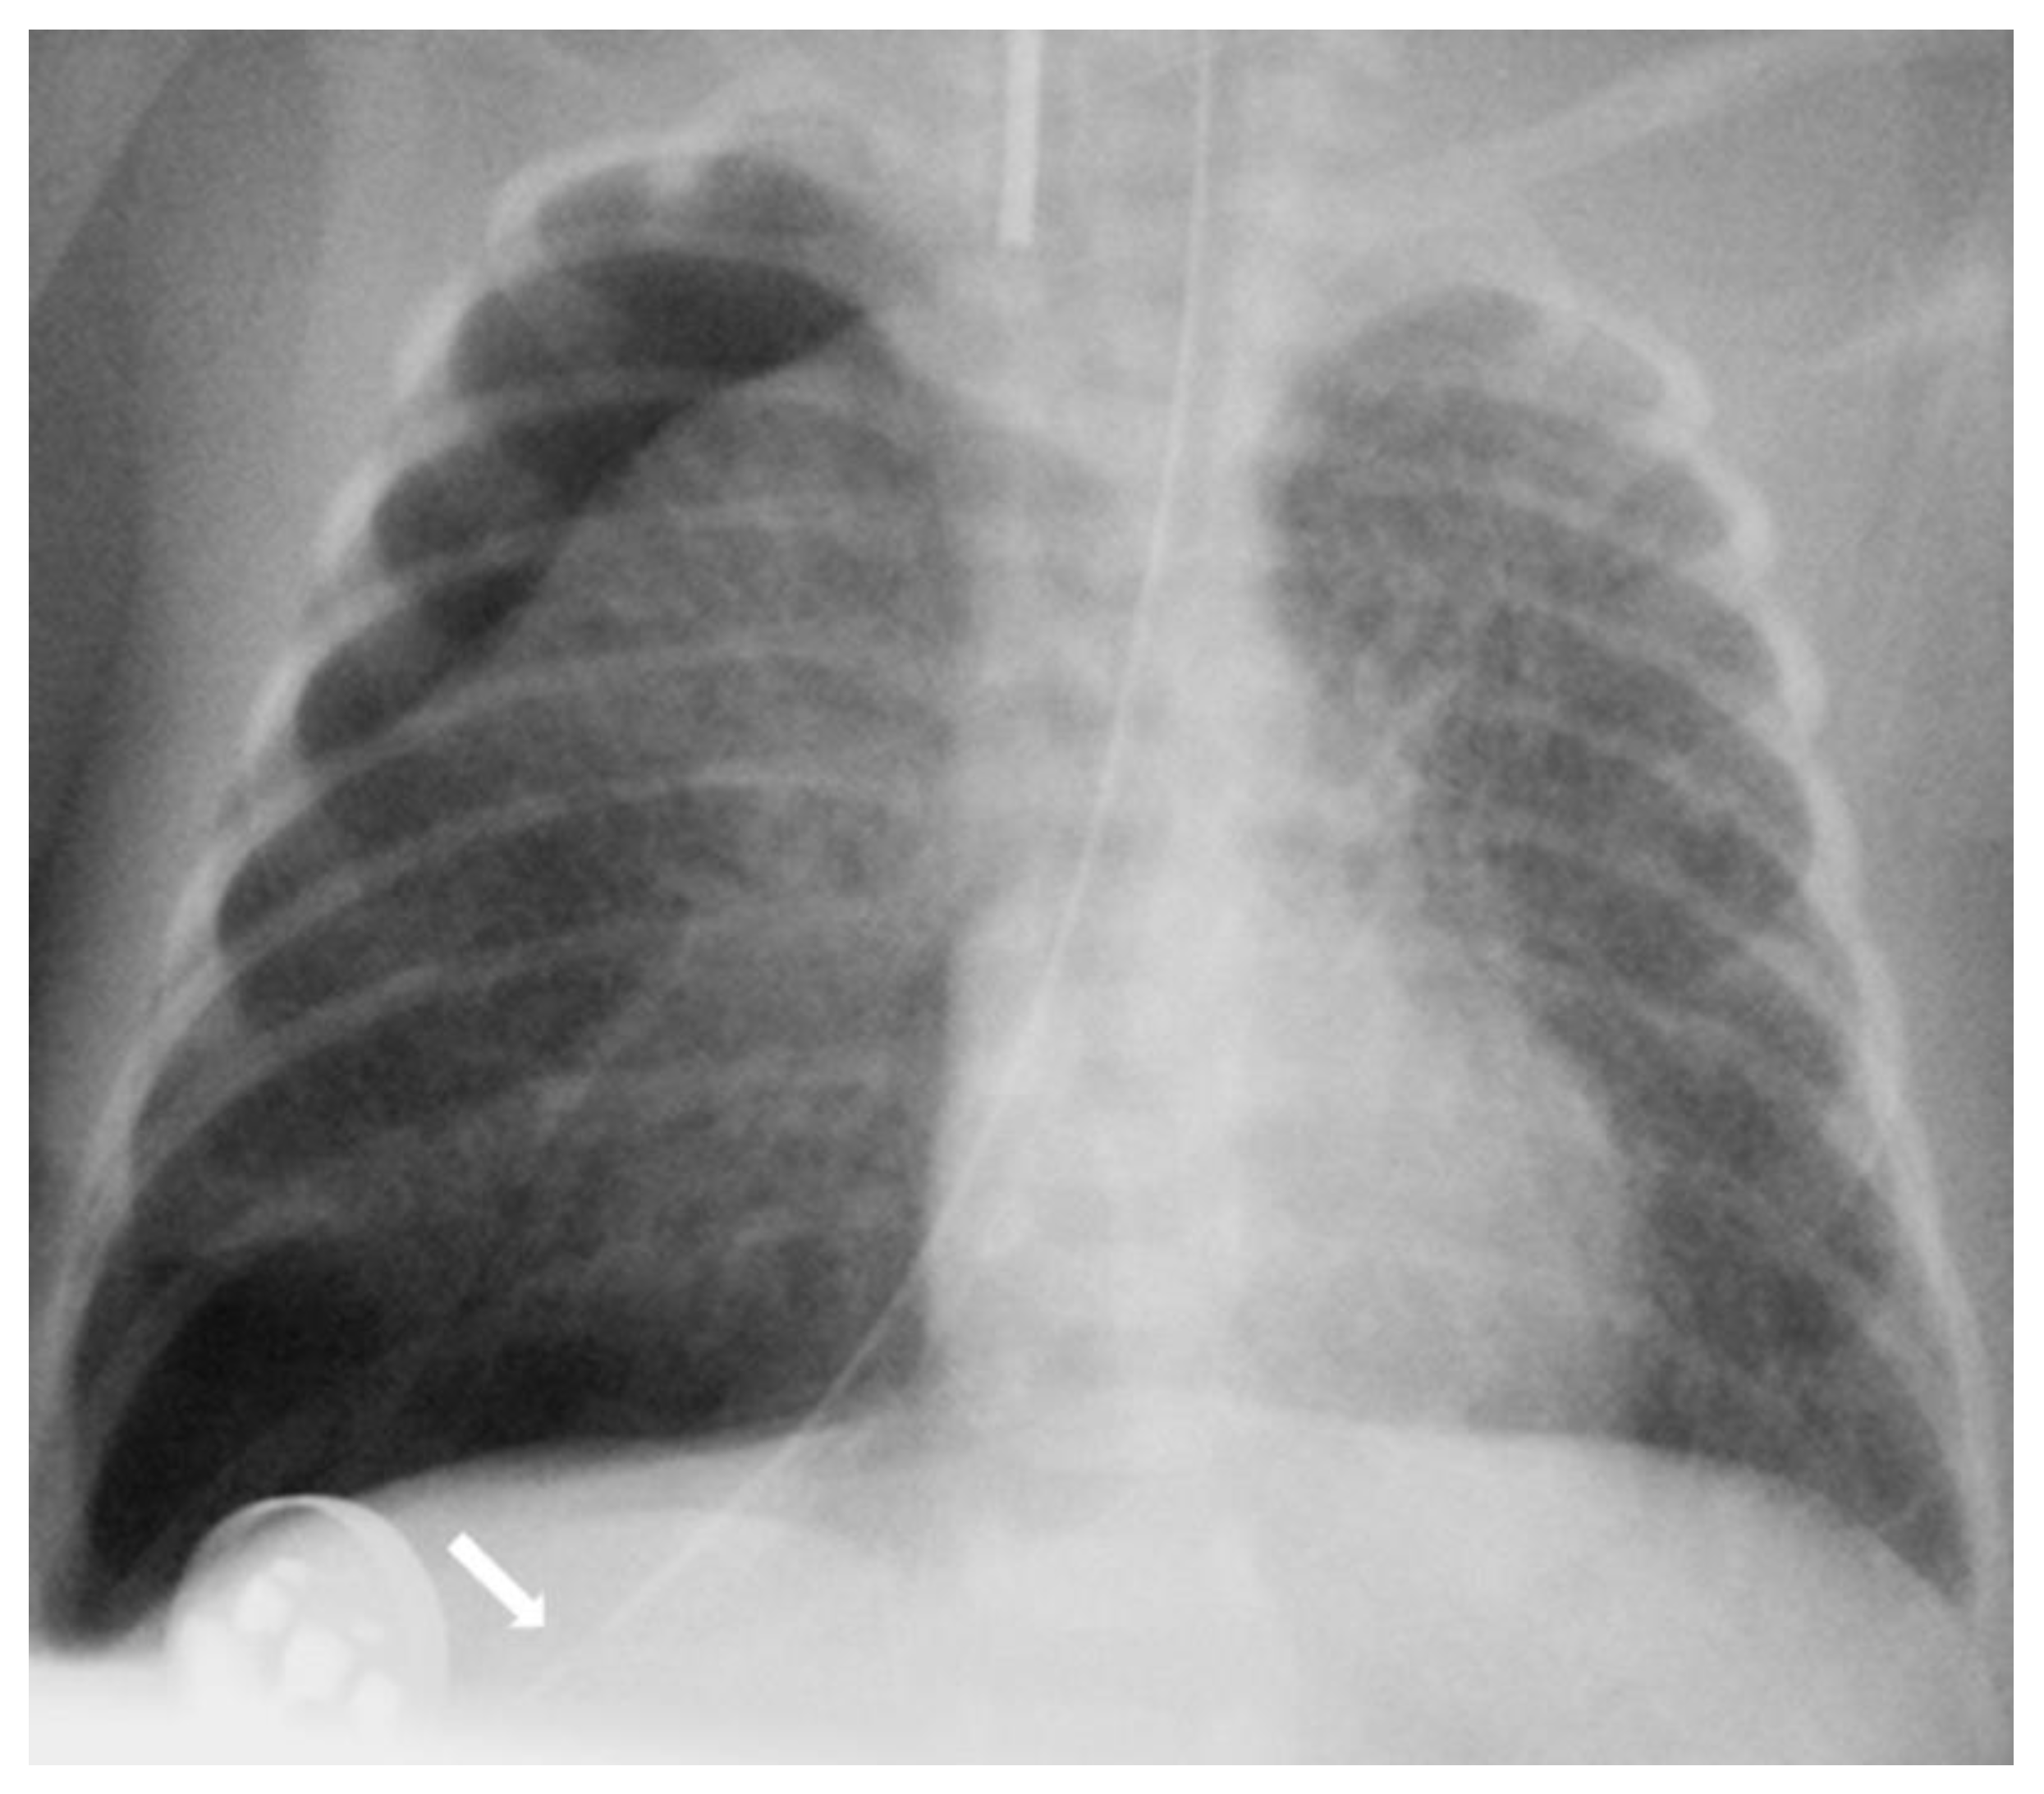

The diagnosis of EP was confirmed via the malposition of the og/ng tube in plain chest X-rays radiographic images. In infants with EP, the chest radiographic image revealed three different malpositions of the og/ng tube. In five infants, the og/ng tube was located in the right pleural cavity (pleural position) (Figure 1), which is usually connected with the pneumothorax or the pneumothorax with pleural effusion, and a radiogram of another two patients indicated mimic esophageal atresia (high position) (Figure 2). In the last three infants, the og/ng tube was located in the abdomen (low position) (Figure 3).

One patient had pneumothorax with pneumomediastinum, four infants had pneumothorax and another of them had milky pleural effusion.

The pleural location of the og/ng tube is usually indicative of a sudden deterioration of the respiratory function, while the low and high position are largely asymptomatic (apart from absence of gastric contents and blood aspiration). Patients with abdominal esophageal perforations may present signs of peritonitis. Mediastinitis may develop as a result of leakage of the esophageal contents.

Radiographs of the chest are useful in demonstrating the presence of the og/ng tube in situ and might reveal three different malpositions of the nasogastric tubes, typically in the right pleural cavity associated with right-sided pneumothorax or pneumomediastinum and sometimes pleural effusion. Common symptoms in this situation are connected with the deterioration of the respiratory status. A chest radiographic image may reveal excessive amounts of air in the mediastinum. The high position of the og/ng tube mimicking an esophageal atresia effect may be due to the presence of a mass created by a false passage of air or milk in the mediastinum [9,14]. The position of the top of the og/ng tube may be helpful in differential exclusion. In true esophageal atresia, it is usually above the bifurcation of the tracheae, while in the mimic esophageal atresia, it is located below the bifurcation. In doubtful cases, esophagoscopy can be conclusive [15]. The presence of gas along the og/ng tube may also be helpful in diagnosing EP. The third possible malposition of the og/ng tube involves the intra-abdominal location, which might be associated with the absence of gas in the intestines. It must be noted that a radiographic image cross-table lateral might, in this case, indicate where the tip of the og/ng tube would appear in the posterior/retroperitoneal space. This would be advisable for a more precise diagnosis. Another complication described by Sorens was mediastinal abscess requiring chest drain insertion [16]. Occasionally, patients with intra-abdominal EP might present symptoms of peritonitis or dysphagia and drooling [1]. In our study, like Elgendys’ study, pneumothorax and septicemia were frequent complications of esophageal perforation [17]. We diagnosed peritonitis in one patient and necrotizing enterocolitis in one patient. In one patient, cardiorespiratory decompression was connected to pleural milky effusion. Chylothorax should be considered and excluded upon differential diagnosis when milk is present in the pleural cavity and milky fluid can be aspirated from the right pleural cavity. Kairamkonda linked chylothorax with esophageal perforation, which may follow when the value of the laboratory fluid analyzed shows a triglyceride level of >1.1 mmol/l with absolute cell count > 1000 cells/mcl and lymphocyte fraction > 80% [18,19,20].

Figure 1. Large right tension pneumothorax with a mediastinal shift. A feeding tube is directed into the right pleura (arrow).